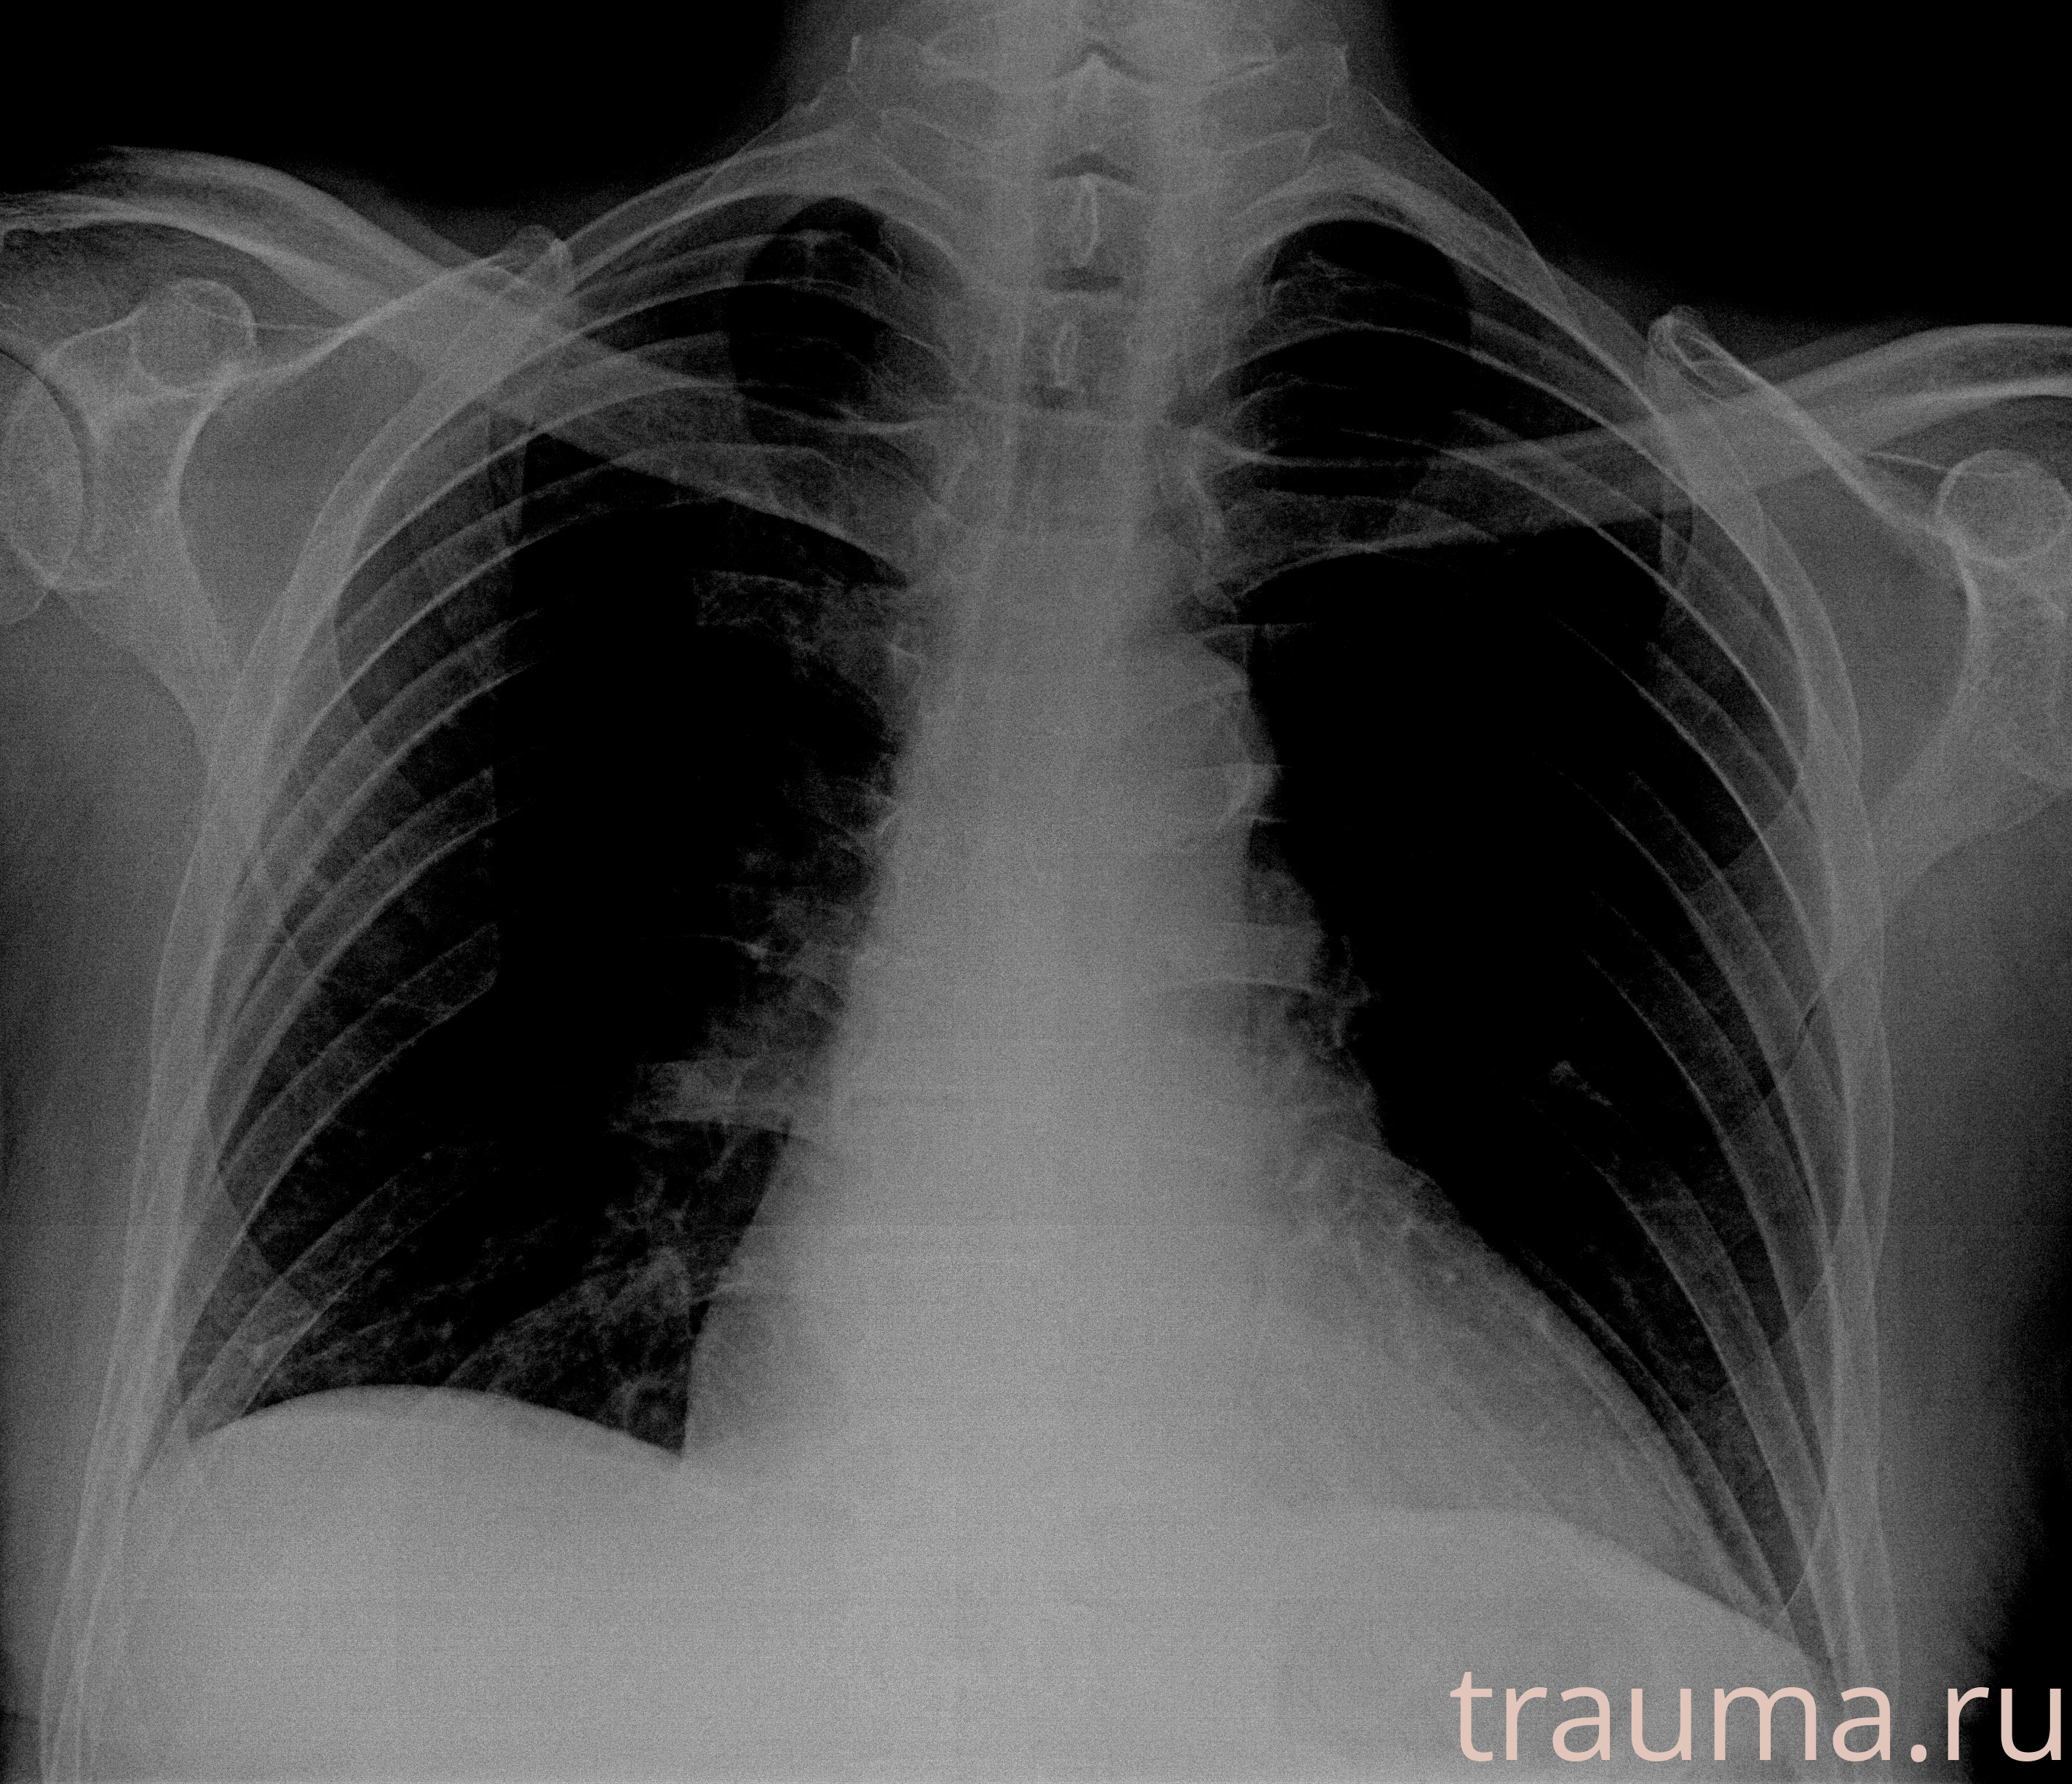

Рентгенограммы

Рентген на дому: по вашему адресу приезжает врач-рентгенолог, травматолог-ортопед с мобильным рентгеновским аппаратом, проводит диагностику травмы или заболевания, делает необходимые рентгенограммы, дает рекомендации по дальнейшему лечению. Получить качественные снимки в домашних условиях возможно благодаря уникальной методике, разработанной МосРентген Центром для института  Склифосовского

Яркость: 1   Контраст: 1   Инвертировать: 0 Увеличение: 1

Перетаскивайте мышь вверх/вниз для контраста, влево/право для яркости. Прокрутка колесом изменяет масштаб. Нажмите Сбросить для возврата к исходному изображению. При увеличении держите мышь в той области, которую хотите рассмотреть.

при переломе шейки бедра и пневмонии от компании МосРентген Центр - партнера Института имени Склифосовского